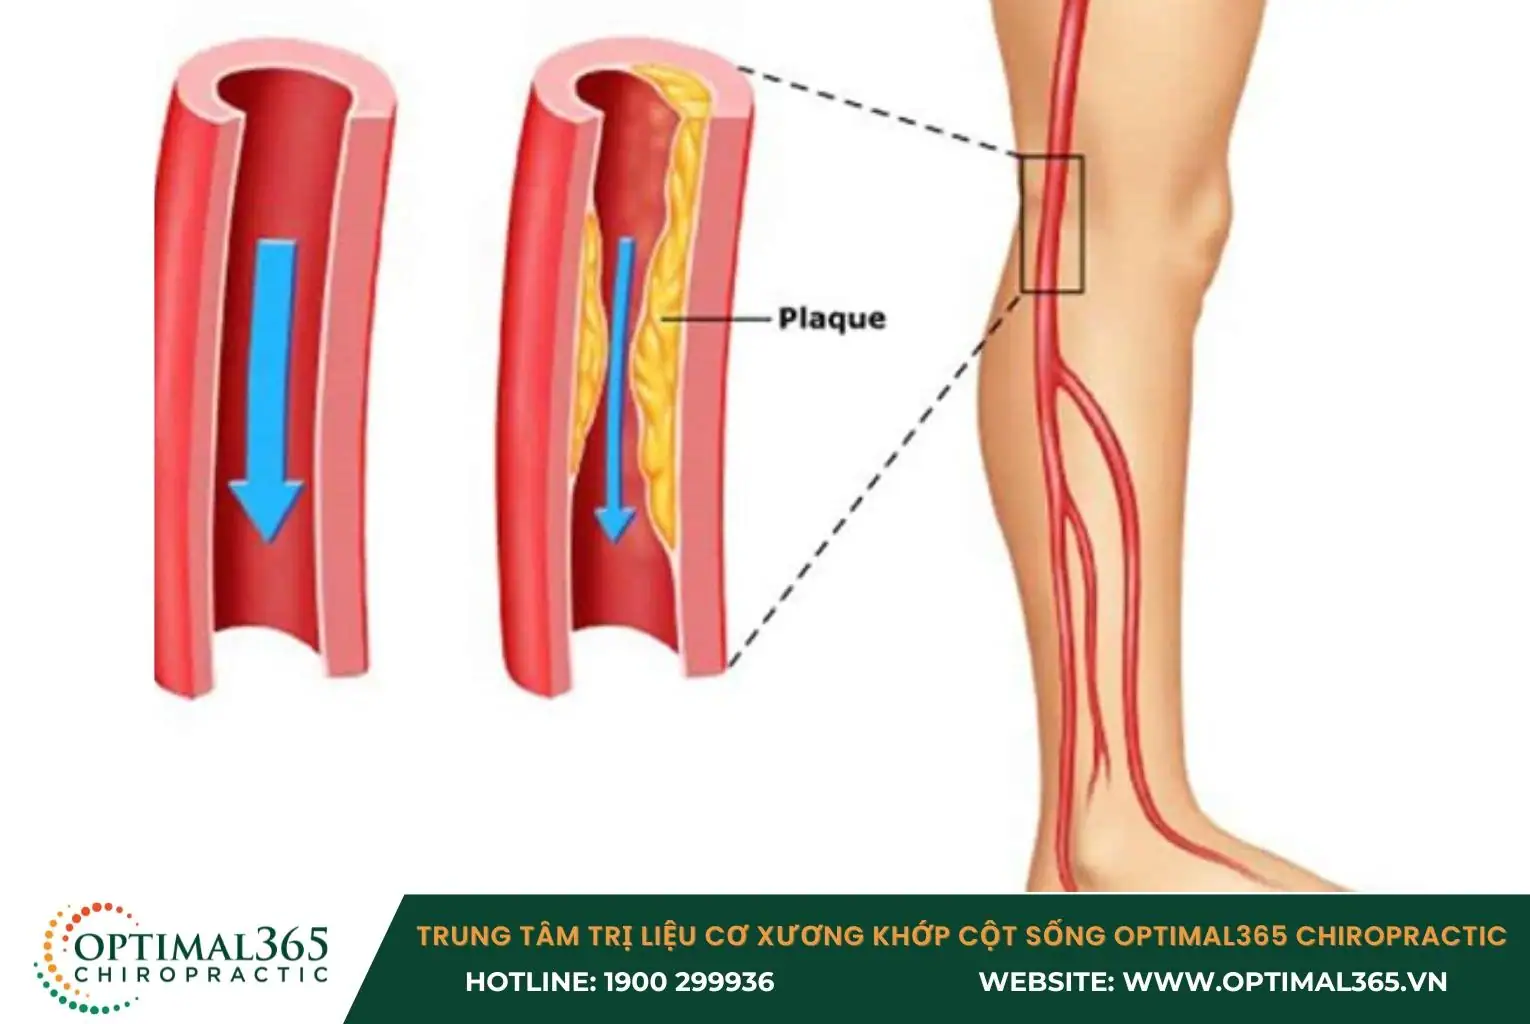

Bệnh động mạch chi dưới

Bệnh động mạch chi dưới (động mạch ngoại biên) xuất hiện khi mảng xơ vữa tích tụ trong động mạch, gây cản trở dòng máu. Mảng xơ vữa bao gồm cholesterol, chất béo, canxi và các thành phần khác trong máu.

Triệu chứng nổi bật nhất của bệnh này là đau chân sau khi đi bộ một khoảng cách ngắn. Ngoài ra, bệnh có thể gây ra các vết loét ở chân, thường bắt đầu từ các chấn thương nhỏ, da khô, vết xước hay nứt nẻ. Trong các trường hợp nghiêm trọng, tình trạng tắc nghẽn mạch máu có thể dẫn đến hoại tử, thậm chí cần phải cắt cụt chi.